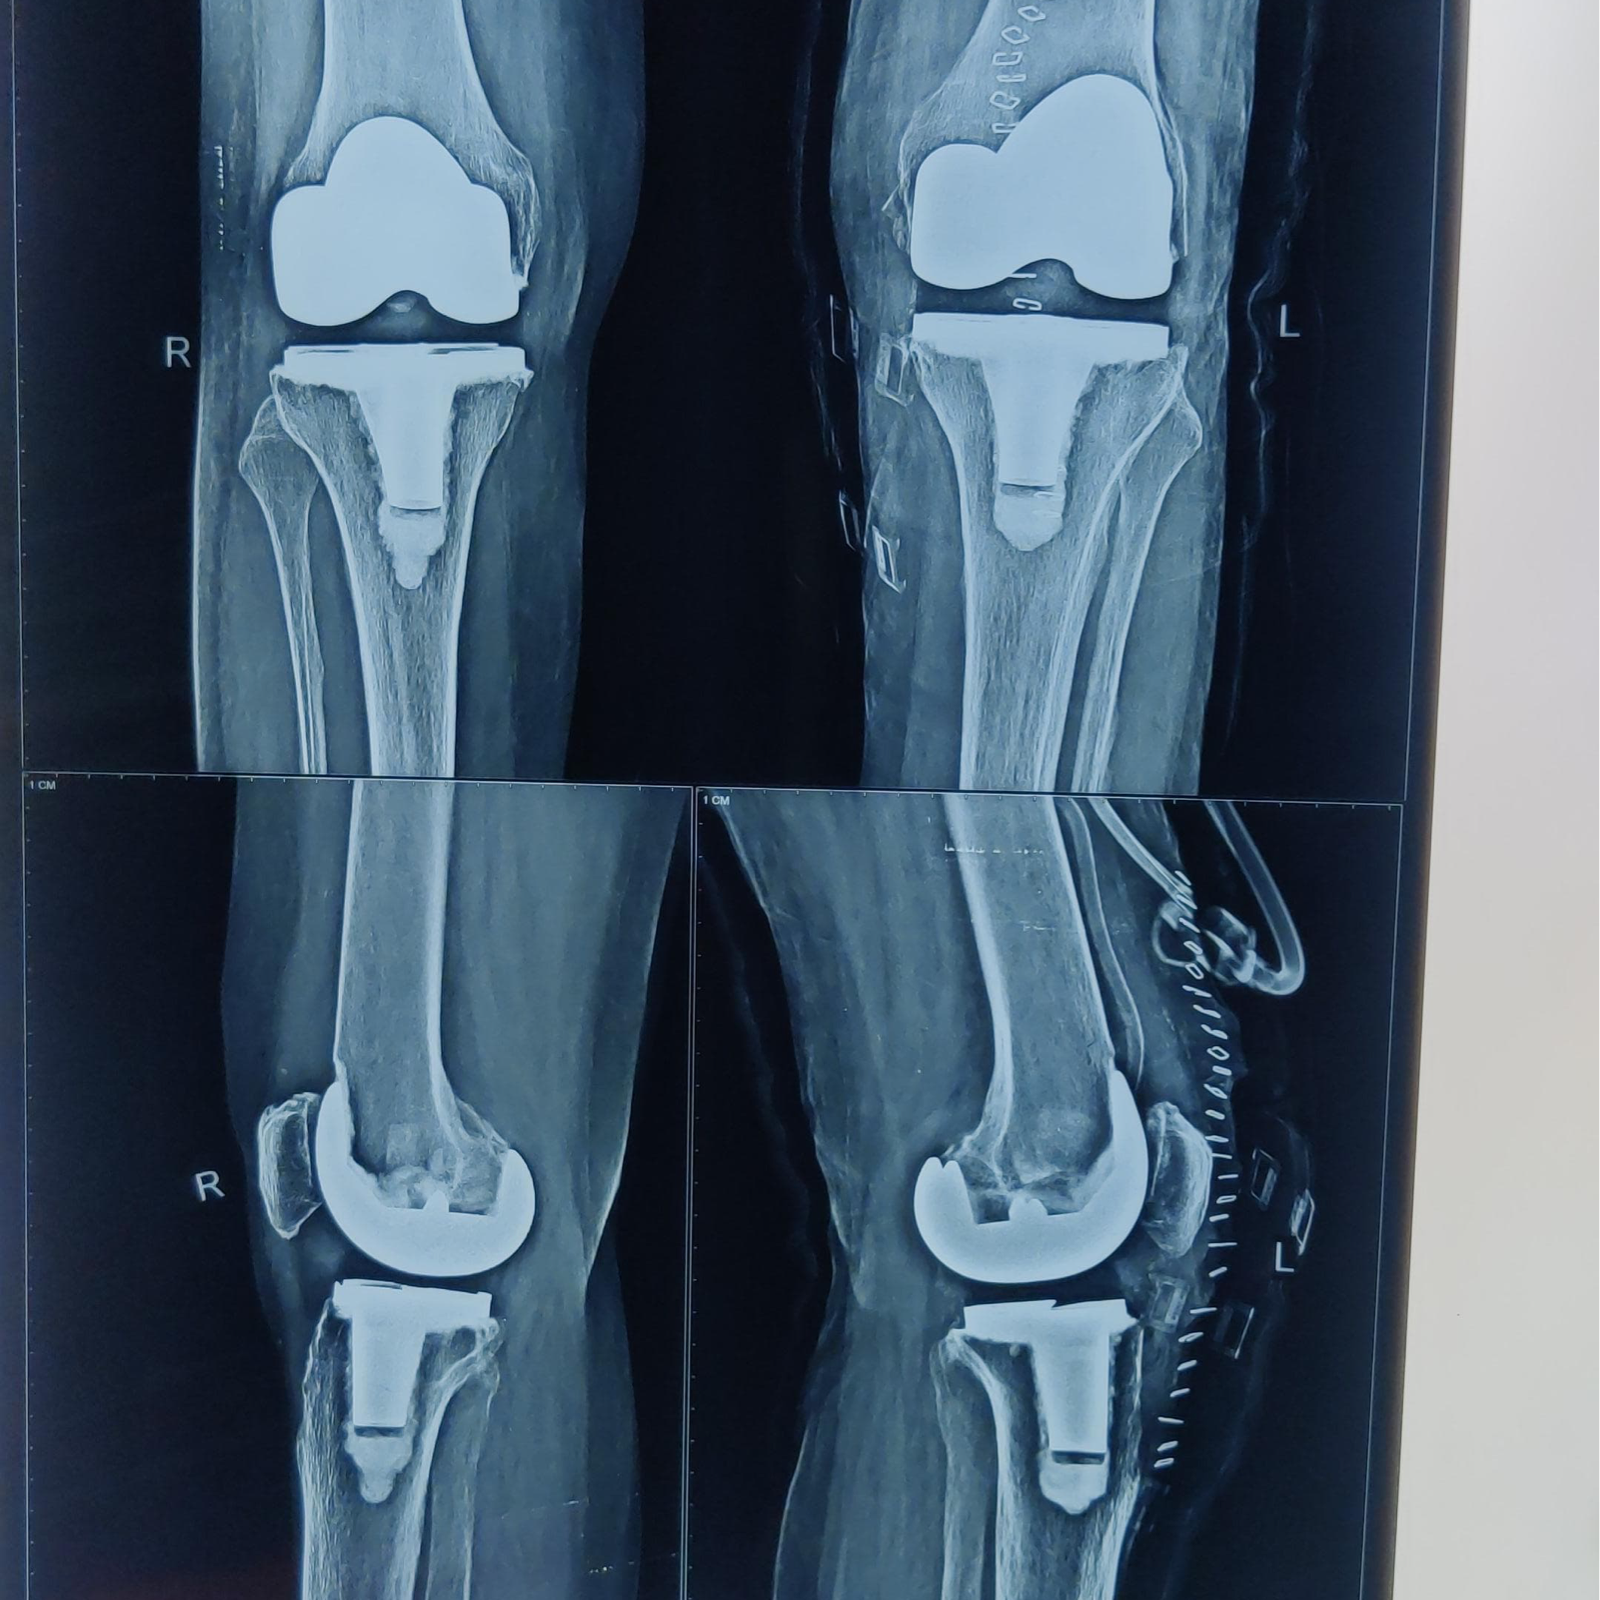

Robotic replacement has revolutionised treatment of Joint replacement as it allows precise cutting of bone with help of robotic machine which allows us to put implant in precise manner and provide better functional results to our patients , thereby accelerating the rehab and faster recovery from surgery .